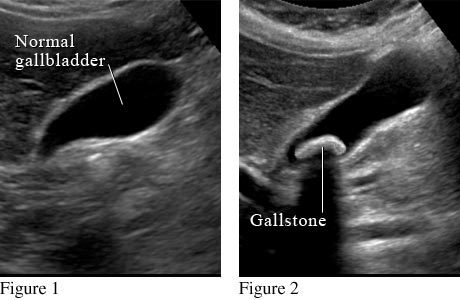

Figure 1 shows a normal gallbladder on ultrasound. Figure 2 shows a large gallstone in the gallbladder.